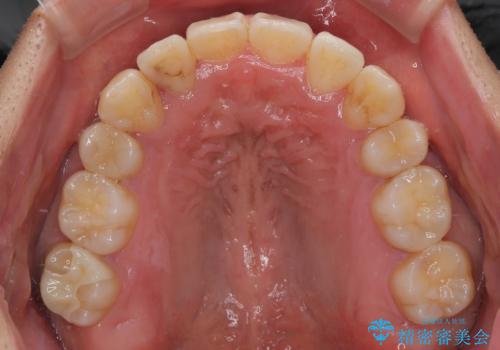

八重歯はきれいに整い、前歯もバランスよく収まり、横顔のラインも自然に改善されました。

治療後、患者様は「思い切り笑えるようになった」と大変喜んでくださいました。